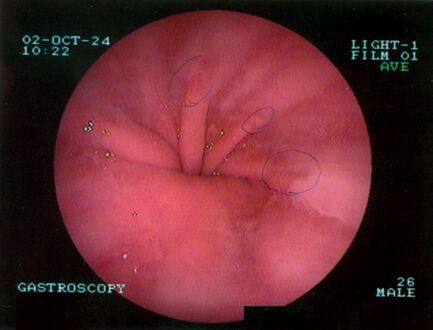

يتم تشخيص فتق الحجاب الحاجز عادةً من خلال سلسلة تصوير الجهاز الهضمي العلوي، التنظير الداخلي، قياس الضغط عالي الدقة، مراقبة درجة حموضة المريء، والتصوير المقطعي المحوسب. يسمح ابتلاع الباريوم كما في سلسلة تصوير الجهاز الهضمي العلوي لرؤية حجم المريء وموقعه وتضيقه. كما يمكنه تقييم حركات المريء. يمكن للتنظير الداخلي تحليل السطح الداخلي للمريء بحثاً عن التآكلات والقرح والأورام.

تنظير الجهاز الهضمي العلوي في وضع الانثناء للخلف يظهر الفتق الحجابي من النوع الأول.